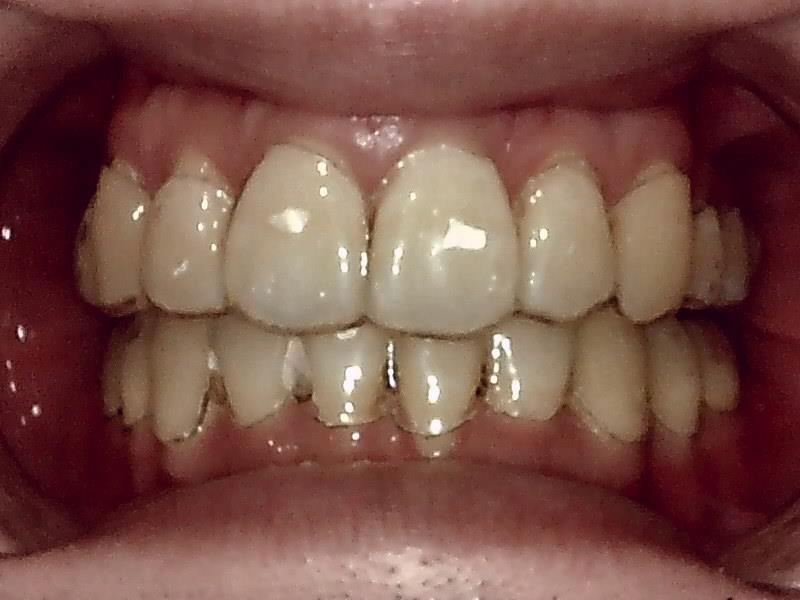

30代後半の女性の親知らずの症例になります。

レントゲン写真の状態を御覧ください。

術前パノラマレントゲン写真

部位:右上8番骨性完全埋伏歯

部位:右下8番骨性完全埋伏歯

部位:左上8番骨性完全埋伏歯

部位:左下8番骨性完全埋伏歯